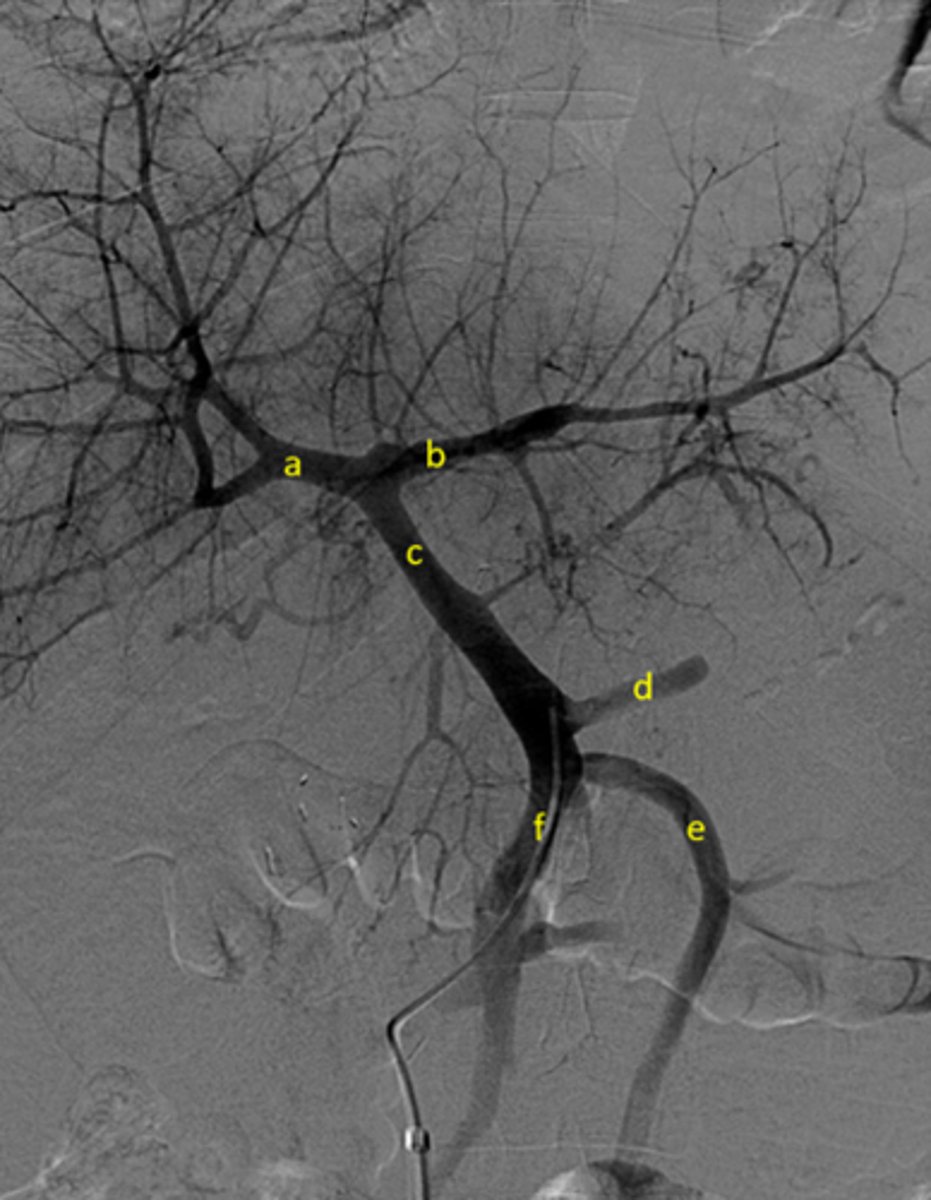

Identify the pertinent anatomy in the following radiograph

A: Right portal vein

B: Left portal vein

C: Portal Vein

D: Splenic Vein

E: Inferior mesenteric vein

F: Superior mesenteric vein

<p>A: Right portal vein</p><p>B: Left portal vein</p><p>C: Portal Vein</p><p>D: Splenic Vein</p><p>E: Inferior mesenteric vein</p><p>F: Superior mesenteric vein</p>

Identify pertinent anatomy of the following radiograph

A: SMA

B: Middle Colic

C:Jejunal arteries

D: Ileal arteries

E: Iliocolic

F: Right colic

<p>A: SMA</p><p>B: Middle Colic</p><p>C:Jejunal arteries</p><p>D: Ileal arteries</p><p>E: Iliocolic</p><p>F: Right colic</p>